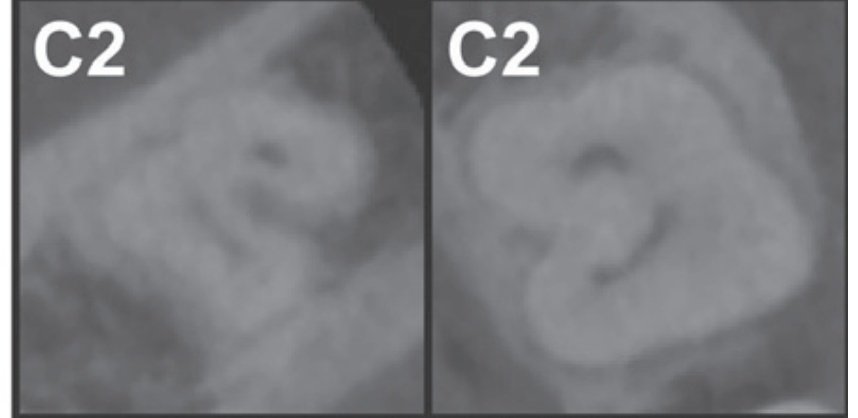

2️⃣ Category II (C2):

The canal shape resembles a semicolon resulting from a discontinuity in the “C” outline, but either angle α or β should be no less than 60°.